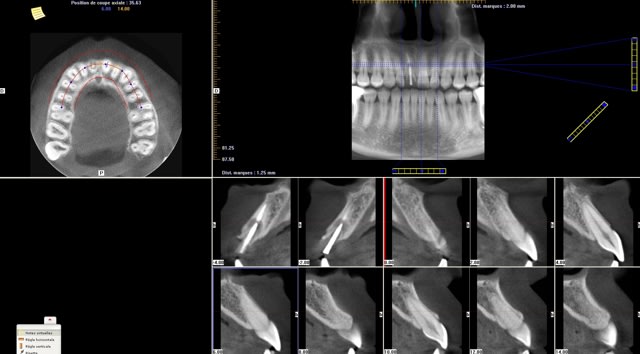

les premières copies d'écran (je ne maîtrise pas encore le logiciel)